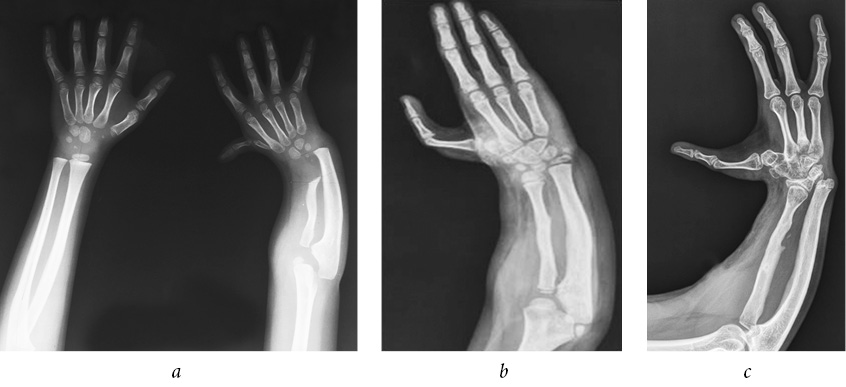

Patient D., 6 years old, had congenital right-sided radial clubhand, hypoplasia of the first finger. For up to 3 years, the patient received conservative treatment (plastering, physiotherapy). At the age of 3 years, compression-distraction apparatus was installed to bring the hand to the middle position. A year later there was a relapse of the hand deviation. During the clinical examination, forearm shortening by 7 cm was noted, and radial deviation of the hand to 32° was registered; it was impossible to passively bring the hand to the middle position, and there was hypoplasia of the first ray (Fig. 1 a). It was decided to restore the radial bone by microsurgical autografting of the vascularized epimetaphys of the second metatarsal bone, including the epiphysial plate. The postoperative period included no abnormalities. Intramedullary wires on the forearm and foot were removed 6 weeks postoperatively.

Fig. 1. Radiograph of the upper limb in patient D. (a) Before the surgical treatment, (b) 3 years and (c) 8 years after microsurgical autografting of the vascularized epimetaphys of the second metatarsal bone, including the epiphysial plate

On examination 3 years (Fig. 1 b) and 8 years (Fig. 1 c) postoperatively, the hand was in the middle position, and mild shortening of the radial bone was observed radiographically.